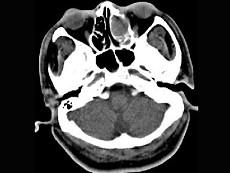

男,34岁,头痛、头晕3个月余,CT检查如图,最可能诊断为 ( )A、筛窦乳头状瘤B、筛窦黏液囊肿C、筛窦炎D、筛窦息肉E、筛窦癌

问题 男,34岁,头痛、头晕3个月余,CT检查如图,最可能诊断为 ( )

选项 A、筛窦乳头状瘤 B、筛窦黏液囊肿 C、筛窦炎 D、筛窦息肉 E、筛窦癌

答案 B